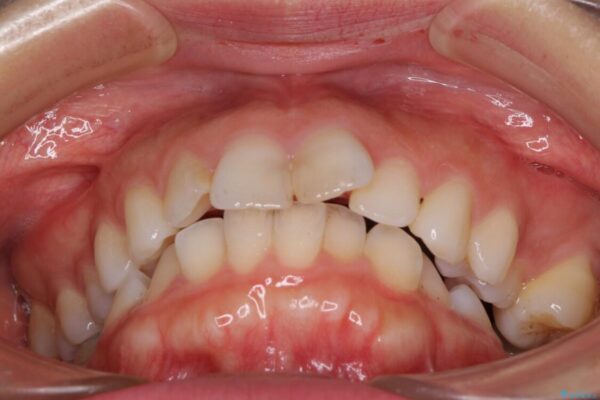

口元の閉じにくさと、奥歯の咬み合わせを気にして来院された患者様です。

左下の大臼歯2本が顕著に舌側に傾斜しているため、まずは奥歯の咬み合わせを改善をし、その後上下左右の第1小臼歯4本を抜歯することで口元を引っ込めながら整えることとしました。

治療前

• 【モニター】出っ歯と咬み合わせを改善 ワイヤー装置の抜歯矯正 治療前画像